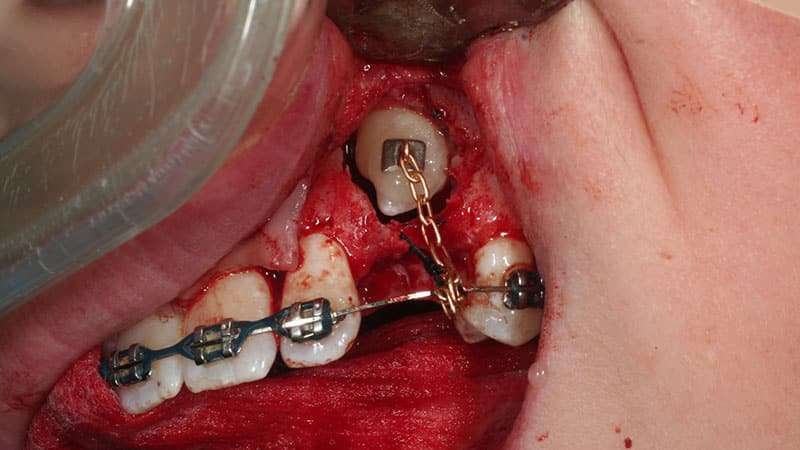

Дистопированные зубы можно исправить с помощью ортодонтических методов, таких как установка брекетов, которые помогают вернуть зубам правильное положение. Этот процесс требует времени, но при наличии терпения он может привести к успешному результату.

Тем не менее, существует возрастное ограничение для лечения, так как брекеты эффективны только до достижения пациентом пятнадцатилетнего возраста. Также рекомендуется удаление дистопированного зуба, если его смещение вызвано недостатком места в челюсти. Если зуб удается вернуть на место, он может быстро вернуться в прежнее положение.